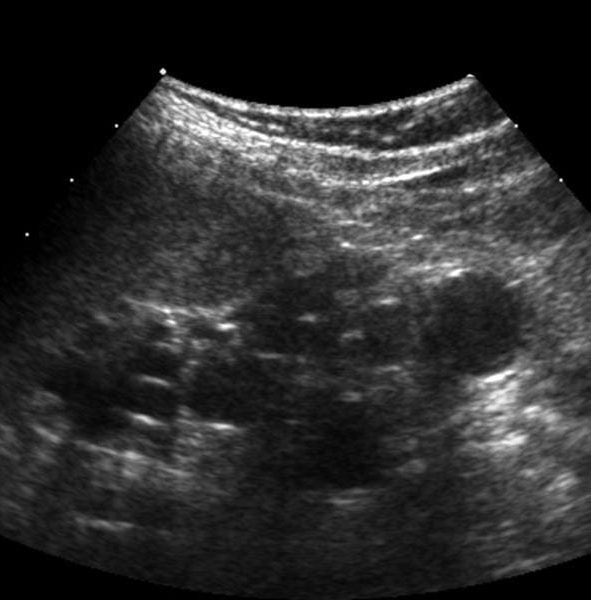

Multicystic dysplastic kidney (MCDK) is a congenital condition where the kidney does not develop normally in the womb and instead forms multiple cysts. Here is an overview of the diagnosis process for MCDK: Prenatal Ultrasound: - First Indication: MCDK is often first suspected during a routine prenatal ultrasound. The ultrasound may show a kidney that is enlarged and contains multiple cysts of varying sizes. Postnatal Ultrasound: - Confirmation: After birth, an ultrasound of the kidneys is typically performed to confirm the diagnosis. The affected kidney will show multiple cysts with little or no normal kidney tissue. 3Differential Diagnosis: - Rule Out Other Conditions: The ultrasound helps differentiate MCDK from other conditions that can cause cystic kidneys, such as hydronephrosis or polycystic kidney disease. Additional Imaging: - Voiding Cystourethrogram (VCUG): This may be performed to check for vesicoureteral reflux (VUR), a condition often associated with MCDK. - Magnetic Resonance Imaging (MRI) or CT Scan: These imaging techniques are less commonly used but may be employed in complex cases to provide detailed images. Renal Function Tests: - Assessing Function: Blood and urine tests may be conducted to assess the function of the other, typically normal, kidney. The overall kidney function is usually preserved if the other kidney is healthy. Genetic Testing: - Investigating Genetic Causes: In some cases, genetic testing may be done to rule out syndromic causes or associated genetic conditions. Follow-Up and Monitoring: - Regular Monitoring: Children with MCDK are usually monitored with periodic ultrasounds to track the size and appearance of the cystic kidney and to ensure the other kidney remains healthy. Diagnosis and follow-up care involve a multidisciplinary approach, including pediatricians, pediatric nephrologists, and urologists, to ensure comprehensive management and monitoring of the condition. Urology Related Doctor In Indore | Kidney Stone Related problems | Urinary Tract Infections (UTIs) Treatment | Urinary Incontinence | Enlarged Prostate (Benign Prostatic Hyperplasia, BPH) Treatment in Indore | Prostate Cancer Doctor in Indore| Bladder Cancer Doctor in Indore| Erectile Dysfunction (ED) Treatment In Indore | Male Infertility Doctor in Indore| Top 10 Urologist in Indore | Best urologist| Urologist near me